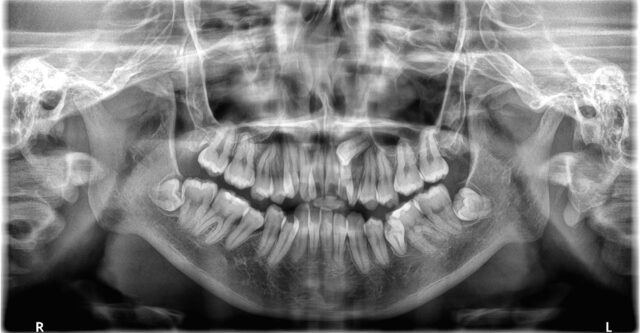

前歯で物が噛めないとご相談があった患者さんです。

上下共に歯と歯が重なっており、いわゆるガチャ歯になっていました。

また、左上の前から3番目には乳歯が残っており、糸切り歯(犬歯)がみられません。

レントゲンを確認したところ、左上の犬歯は顎の骨の中に埋まっておりました。

相談した結果、犬歯は残念ながら抜歯し右上の第1小臼歯(4番目の歯)の抜歯を行い、下顎は左右の第1小臼歯と親知らずを抜いて治療を行いました。